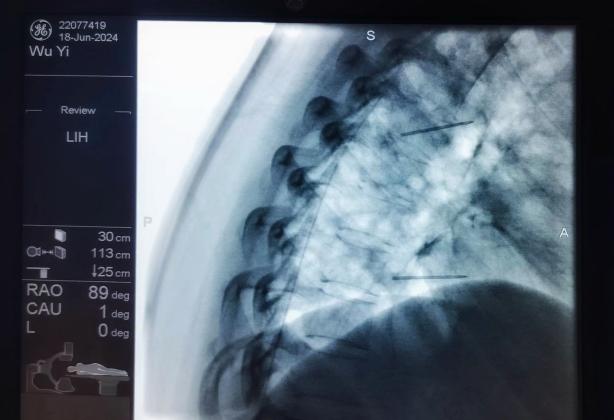

膠原酶椎間盤化學(xué)溶解術(shù),是在影像引導(dǎo)下(C型臂X線機(jī)或CT),將膠原酶準(zhǔn)確地注射到突出的椎間盤內(nèi)及其周圍,使突出的椎間盤溶解并吸收,解除其對神經(jīng)根的壓迫,進(jìn)而緩解癥狀。

椎間盤射頻消融術(shù)、膠原酶椎間盤化學(xué)消融術(shù)